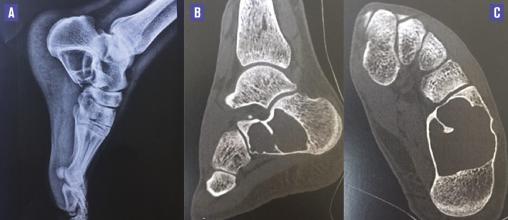

Ce patient de 30 ans consultait à la suite d’une chute sur le talon gauche. L’examen révélait une douleur à la palpation des parties molles en regard du calcanéum, une rougeur et un œdème localisé sans hématome. Une radiographie du pied a permis de découvrir, fortuitement, une vacuité radioclaire du calcanéum, liée à un kyste osseux simple de grande taille, confirmé par un scanner, sans fracture associée (figure).